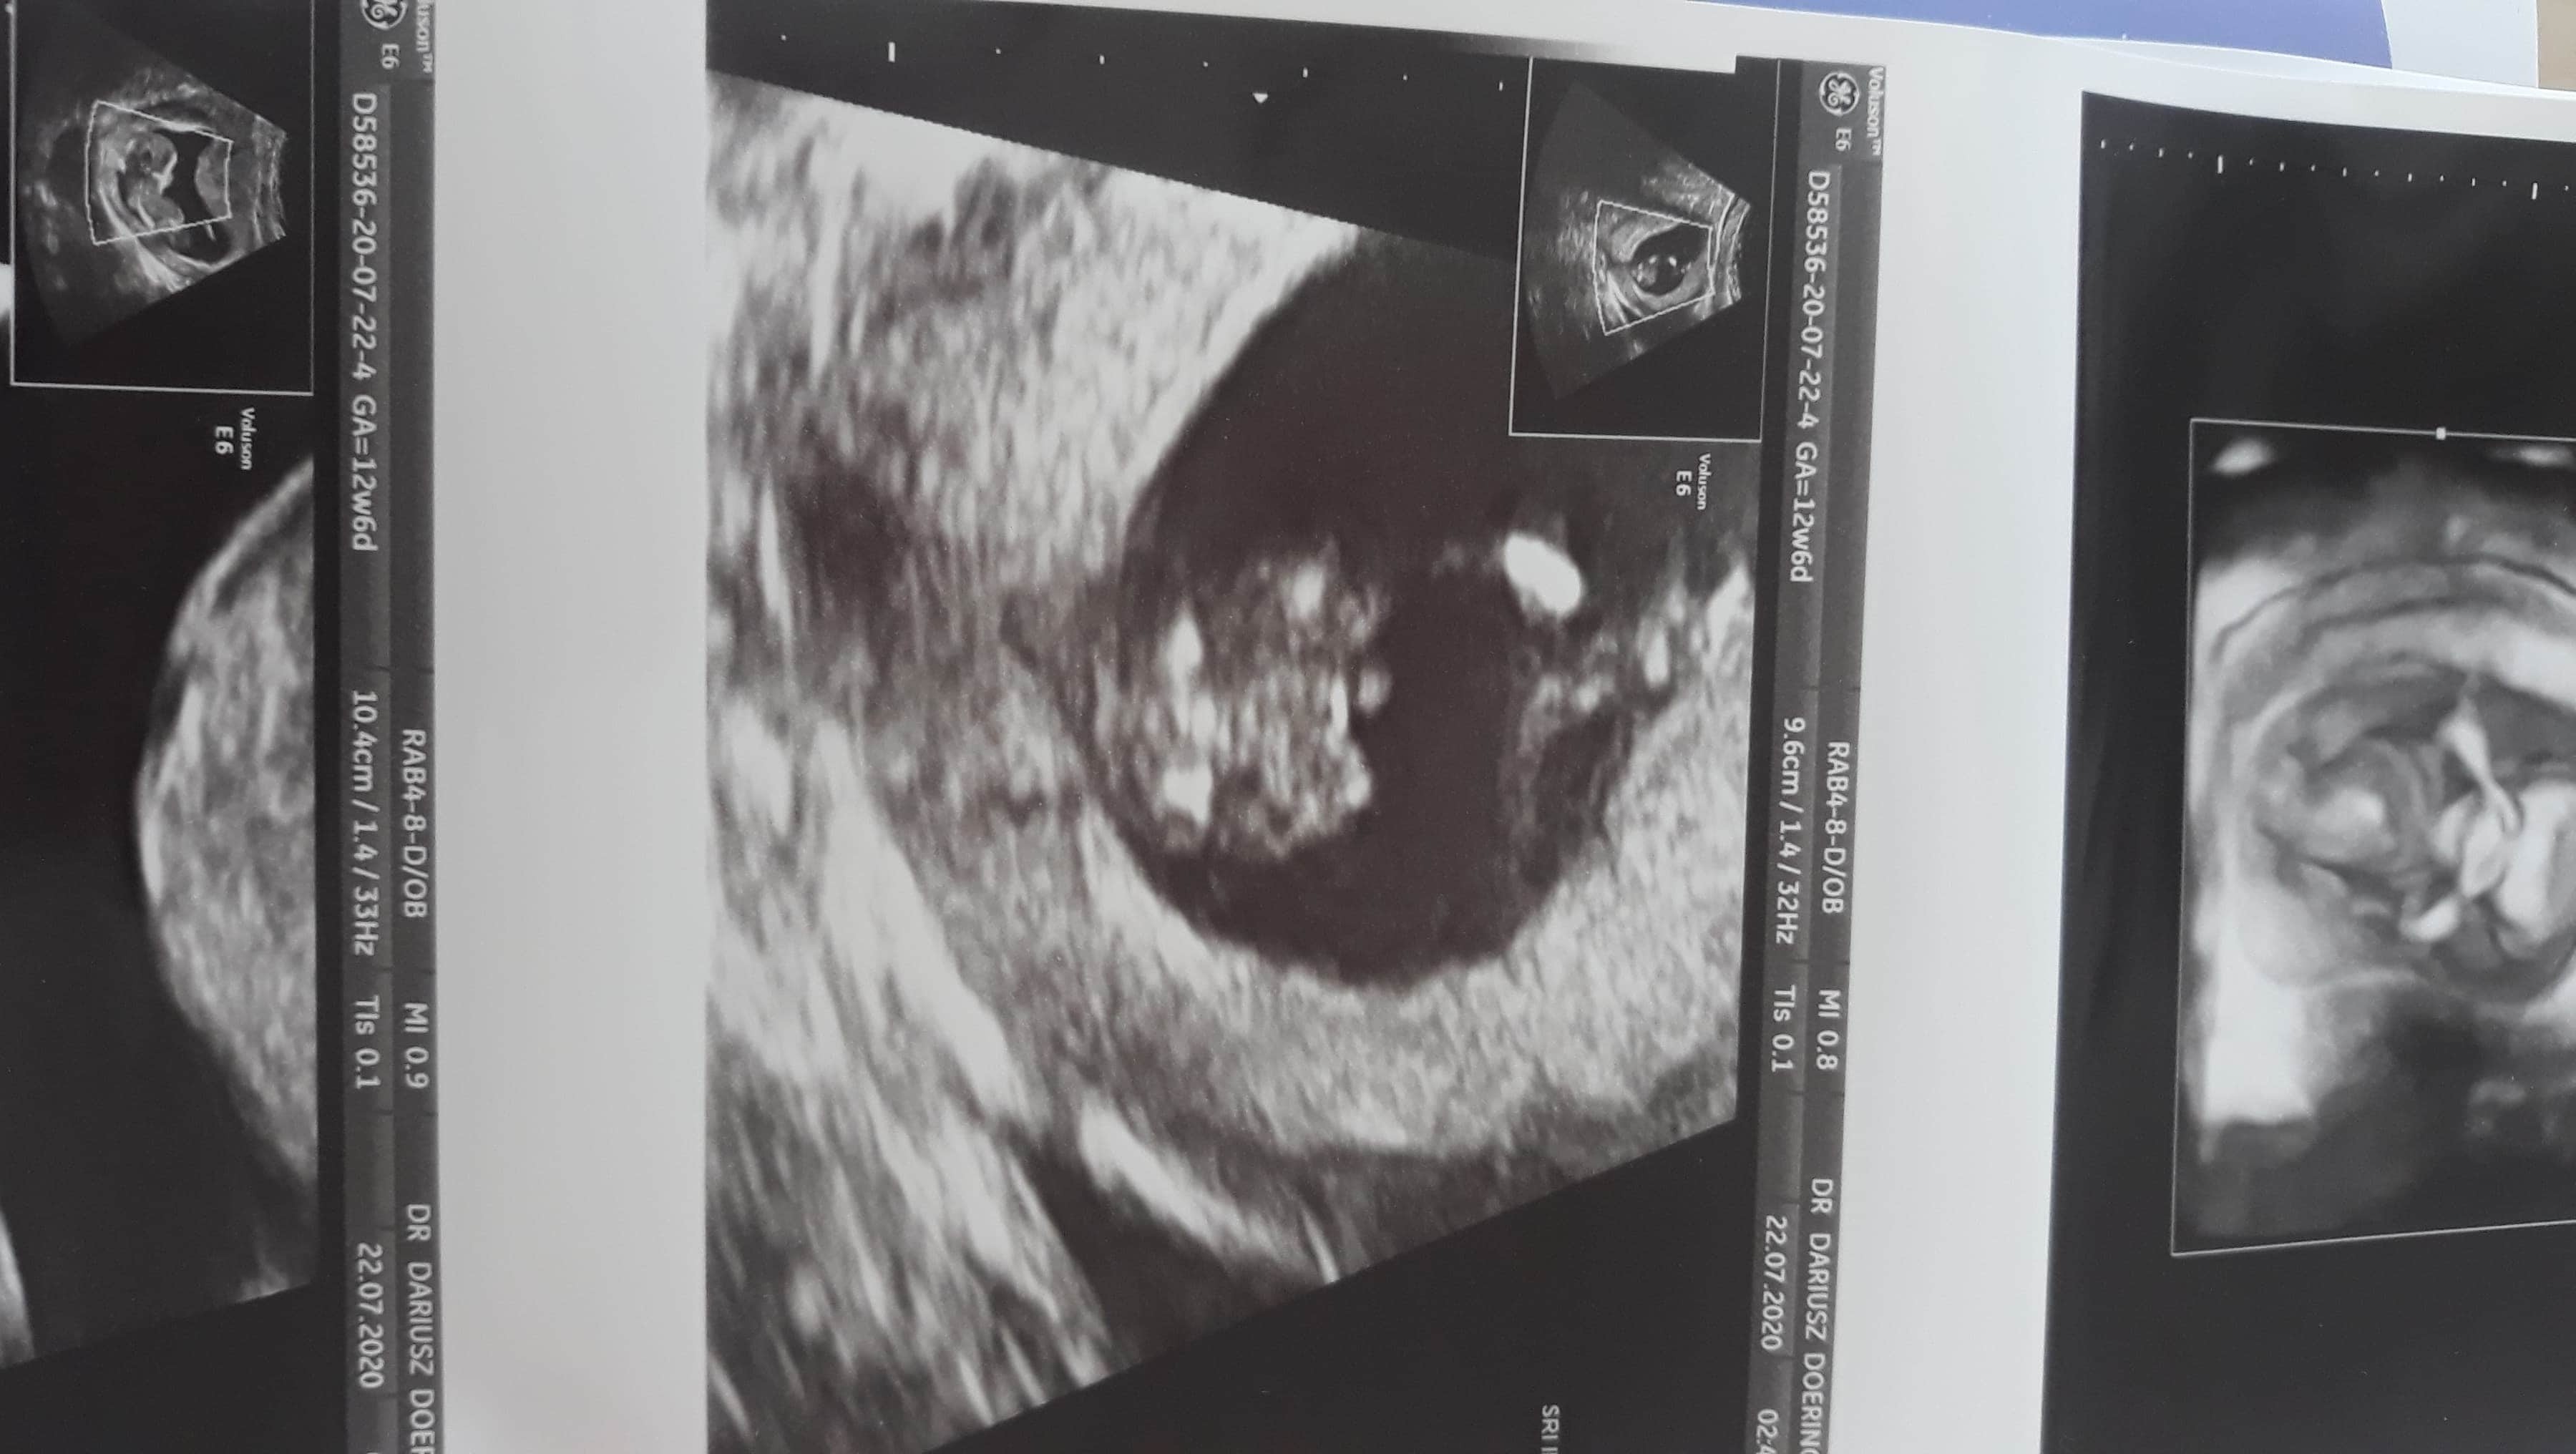

Cześć dziewczyny,

Jak obstawiacie - chłopiec, czy dziewczynka? :)

Załączniki

• IMG_20200715_132028.jpg

IMG_20200715_132028.jpg

1,1 MB · Wyświetleń: 195

• 15948122551844865087328945464018.jpg

15948122551844865087328945464018.jpg

1,1 MB · Wyświetleń: 177